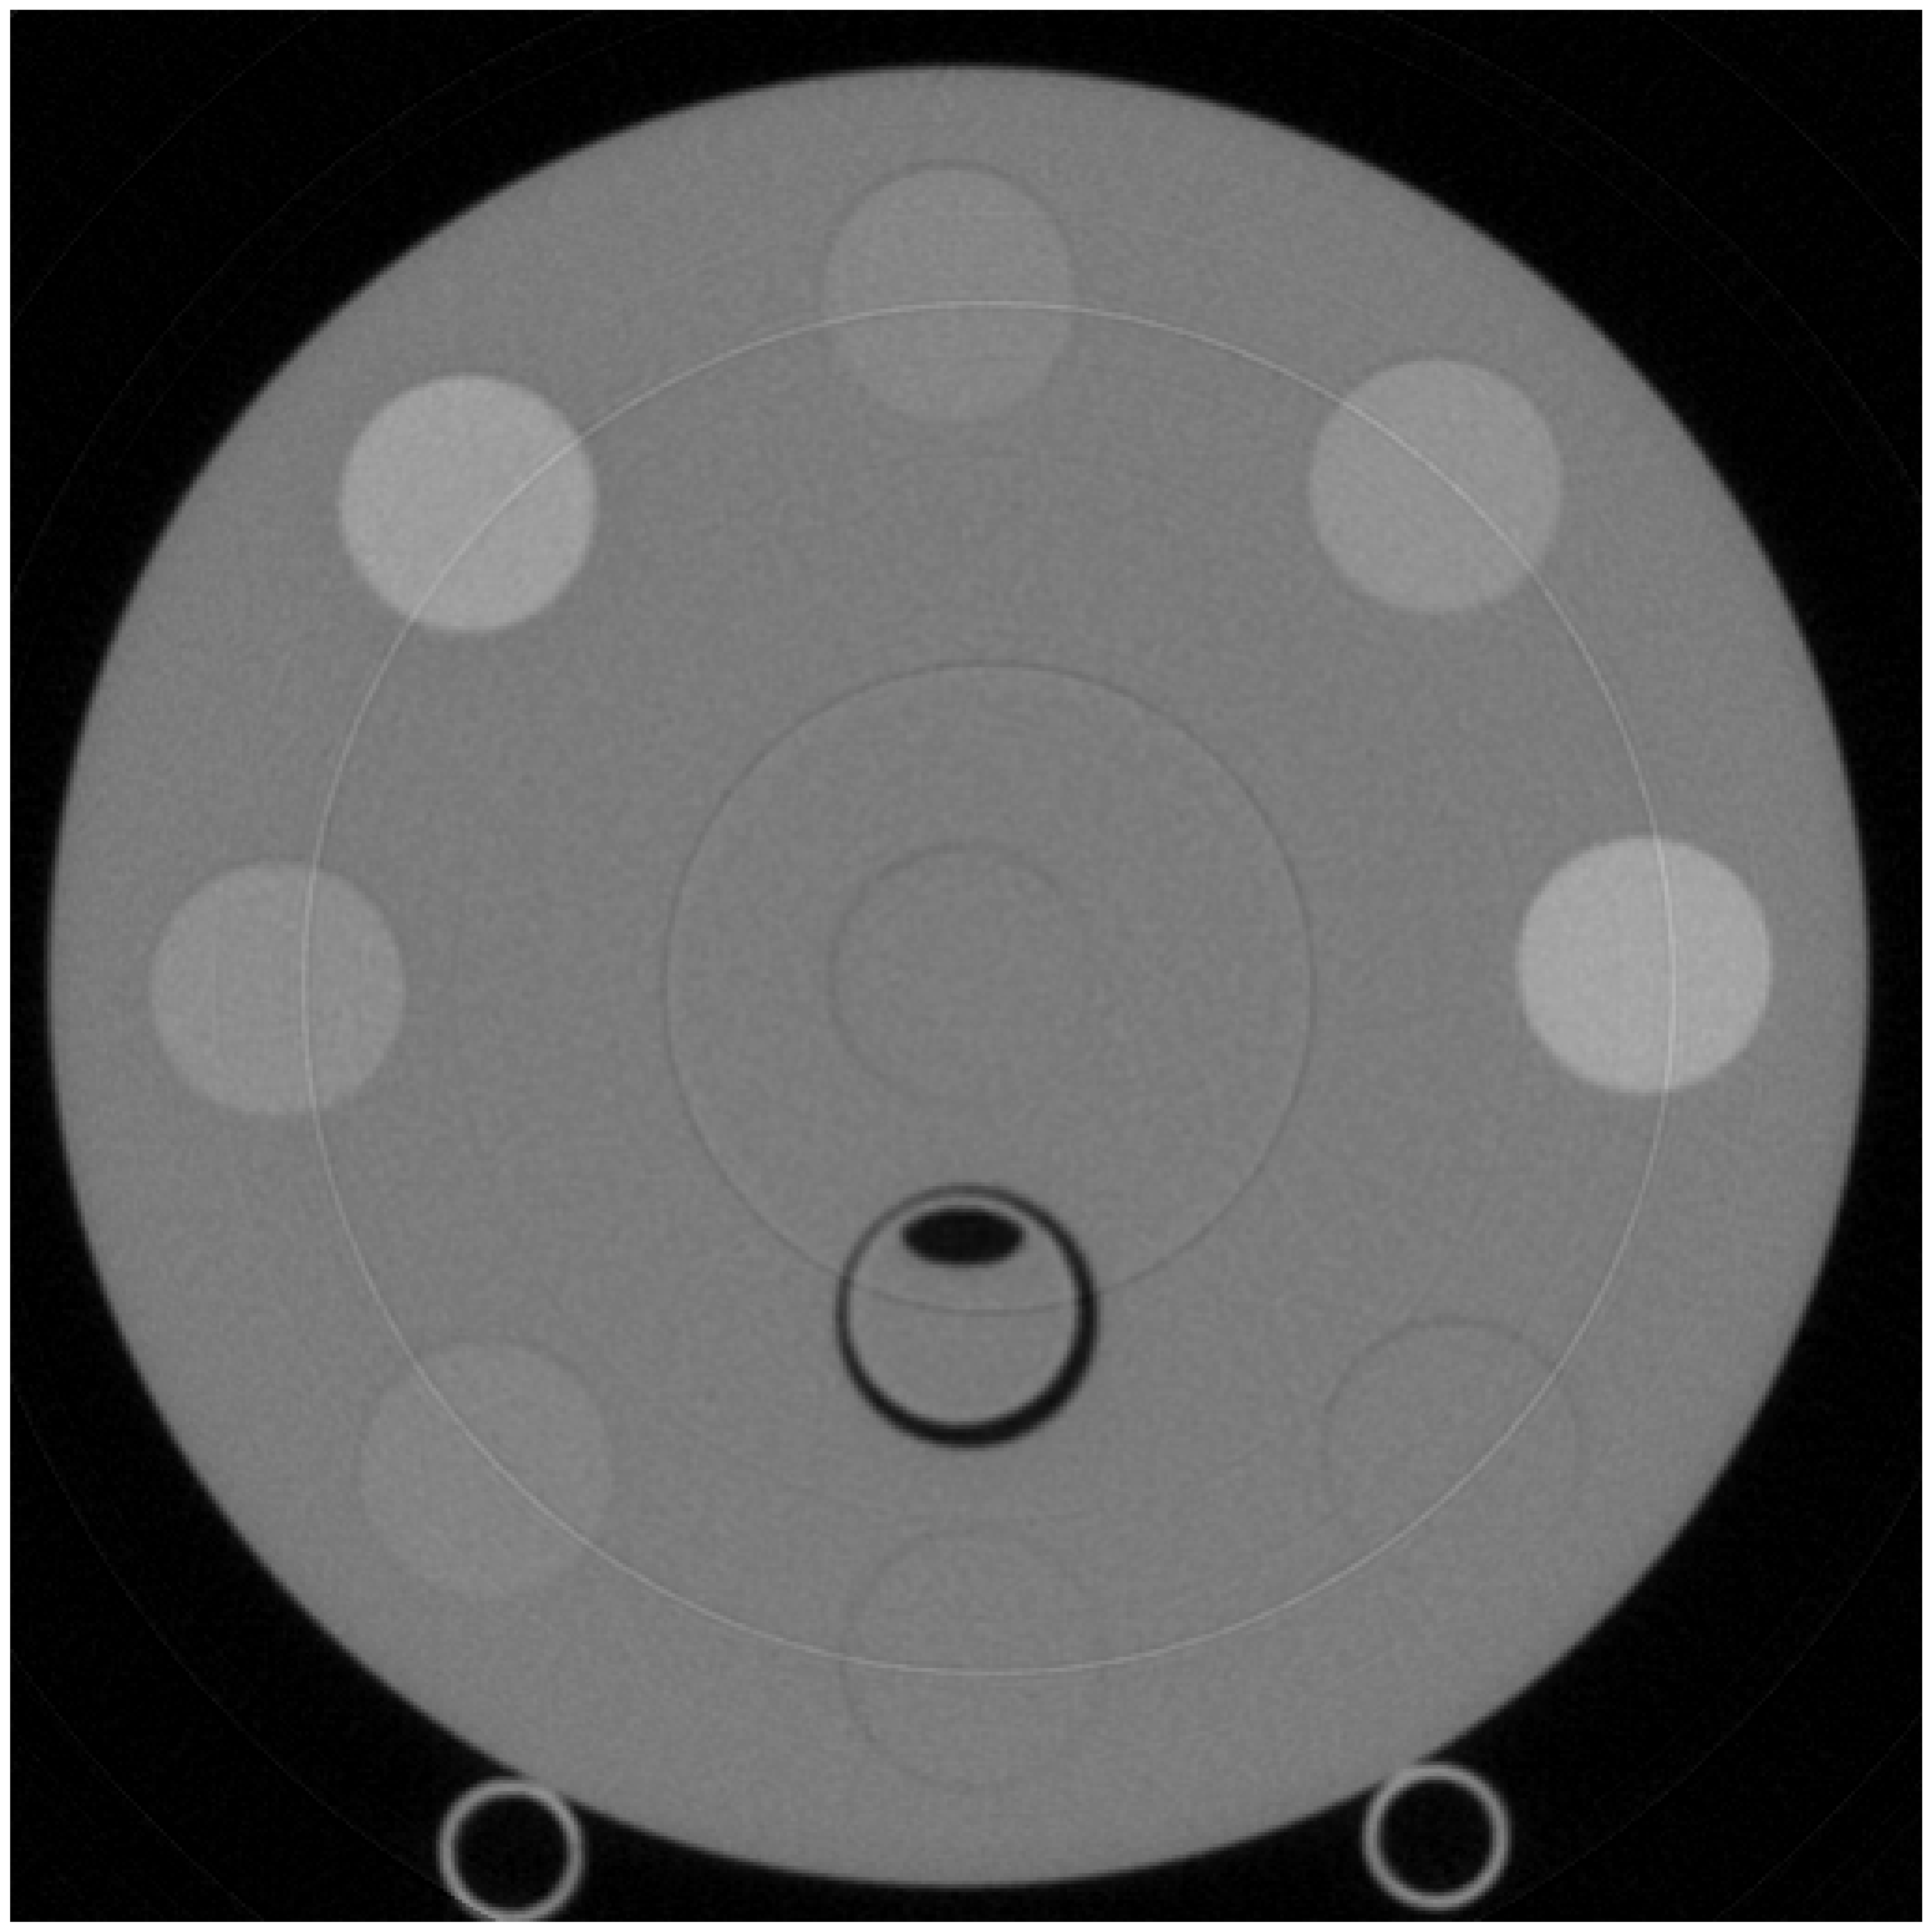

For experiments with measured data, we used data obtained from scans of the Gammex Multienergy phantom, without the body ring. This phantom contains iodine inserts with various densities. The DFOV is 40 cm which is then cropped to a size of to show just the relevant region.

Figure 3 shows a reconstruction, from actual measured data, for the same phantom with the proposed algorithm (bottom row) as well as a comparison to the calculated MLE (top row). The MLE estimates are obtained with to ensure convergence. The proposed method also employs MLE estimate to initialize . However, in this case, we found to be sufficient, saving the computation time. This demonstrates that we can reduce the number of iterations needed to calculate an approximate value for the MLE while still achieving significant noise reduction. For the prior model to denoise the measured data, we decorrelate the PE and PVC pathlength sinograms by rotating these in material space and applying Gaussian filters of standard deviation 6.0 and 1.5, respectively. We then rotate the pathlength sinograms to their original orientation. Lastly, we clip the values to the limits of the calibration space. Note that this is a more complex denoiser compared to that applied to the simulated data. This demonstrates the modularity of our method with the ability to mix and match denoisers depending on application. Figure 3 shows a visual comparison in noise between the MLE and the MACE results.

Figure 4(a) labels circles used for quantitative evaluation. Table 1(a) shows the means and standard deviations for the selected circles. As expected from Figure 3, our method shows a similar mean but a significant reduction in standard deviation compared to the MLE quantitatively.

Figure 3 reconstructions have thin, bright and dark concentric rings, which are artifacts due to limitation of the detector prototype employed. These measurements are removed in practice, but such removal is not part of this proposed method. Importantly, the proposed method gives flexibility to scale the parameter in a band around these detector elements to remove such artifacts, but the fine tuning of is not performed in these results.